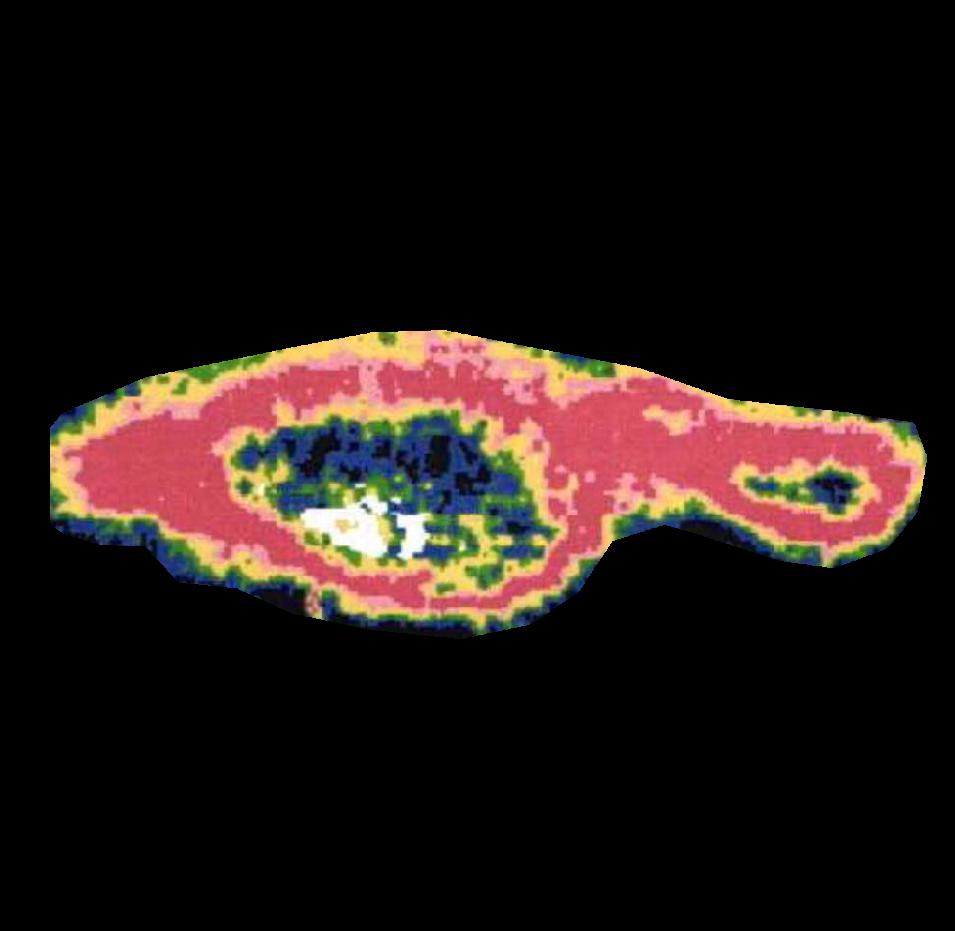

4 Quantitative Analysis

We evaluated the performance of the BAM in segmenting burn areas from images using a dataset of manual segmentations validated by clinicians of burn areas from 2D colour images. We also compared BAM against Laser Doppler Imaging (LDI) results, the gold standard for assessing the depth and healing potential of burns. LDI generates a map of the blood flow in different parts of skin (including the burn areas) using laser Doppler technology. During scanning, laser light enters the skin tissue and is scattered by moving blood cells in the tissue. As a result, the frequency of the light changes according to the Doppler effect; the higher the speed and concentration of moving blood cells in a tissue, the higher the amplitude of the laser Doppler signal. This blood flow image is used to calculate three categories of healing potential for burn wounds; 1) less than 14 days, 2) 14 to 21 days, and 3) more than 21 days Med (2021)Hoeksema et al. (2009). The colors of a blood flow image and their corresponding healing potential categories are illustrated in Figure 6.

Table 2 (top) reports four different metrics for comparing BAM segmentations with manual segmentations and LDI masks. Briefly, pixel-wise accuracy reports the ratio of correctly classified pixels to the total pixels. Pixel-wise sensitivity quantifies the ratio of correctly classified burn pixels to all the actual burn pixels representing the true positive rates. The pixel-wise specificity measures the ratio of correctly classified non-burn pixels to all the actual non-burn pixels representing the true negative rates. Finally, Jaccard Index/IOU measures the degree of overlap between ground truth segmentations (here manual segmentations or LDI segmentations) and predicted segmentations (here BAM segmentations). It is an important measure of performance as it considers both false positives and false negatives.

In addition to evaluating the BAM segmentations against the manual segmentations and the LDI scans, we examined how much improvement the BAM segmentations achieve in comparison to the Grad-CAM heatmaps. The reason for this comparison is the fact that the BAM heatmaps are generated based on the Grad-CAM heatmaps. Therefore, if the Grad-CAM heatmap fails to correctly identify the burn region in the image, BAM segmentations will also fail in generating a high-resolution heat map that highlights the burn region. In contrast, if the Grad-CAM heatmap highlights the correct region (even partially), then the BAM heatmap will be able to generate a high-resolution heatmap that highlights the burn.

Table 2 (bottom) reports the same four metrics when comparing the Grad-CAM heatmaps with the manual segmentations as well as LDI scans. For the purposes of performing this evaluation, we convert the Grad-CAM heatmaps into binary segmentations by masking them at . It is evident from Table 2 that significant improvement of Jaccard Index is achieved by moving from the Grad-CAM segmentations to the BAM segmentations. Additionally, it is shown that for Grad-CAM segmentations specificity is very high while sensitivity is very low. This means that Gradm-CAM segmentations are good at partially highlighting the burn area only. However, BAM segmentations improve these partial segmentations and therefore achieve a better balance of sensitivity and specificity.